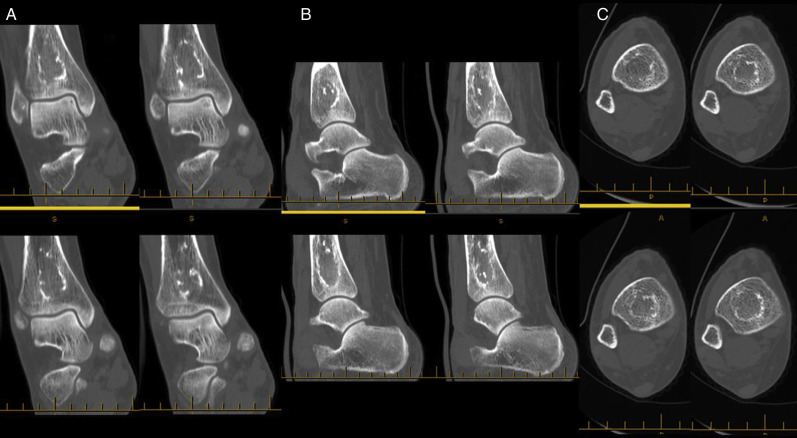

The previous surgeon she had consulted had ordered a magnetic resonance imaging study and diagnosed AVN of the bilateral distal tibias (Fig. 1 ). Subsequent magnetic resonance imaging studies showed ON in the left calcaneus and right humerus. Only her right tibia was symptomatic. For preoperative planning and to rule out any pathologic fractures, a computed tomography scan was ordered (Fig. 2 ).

Fig. 2.

Computed tomography study showing lesions of avascular necrosis in the coronal (A), sagittal (B), and transverse (C) slices of the diaphyseal–metaphyseal junctions of the right tibia.